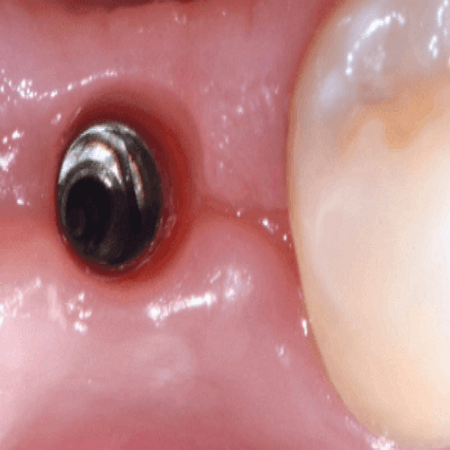

4. 지대주 연결

시간이 지나 고정체가 잇몸의 조직과 잘 결합되어 임플란트를 지탱할 준비가 되었다면 고정체에 지대주를 연결해주는데요. 볼트 쪼듯이 간단하게 쪼아만 주면 되는 단계입니다.